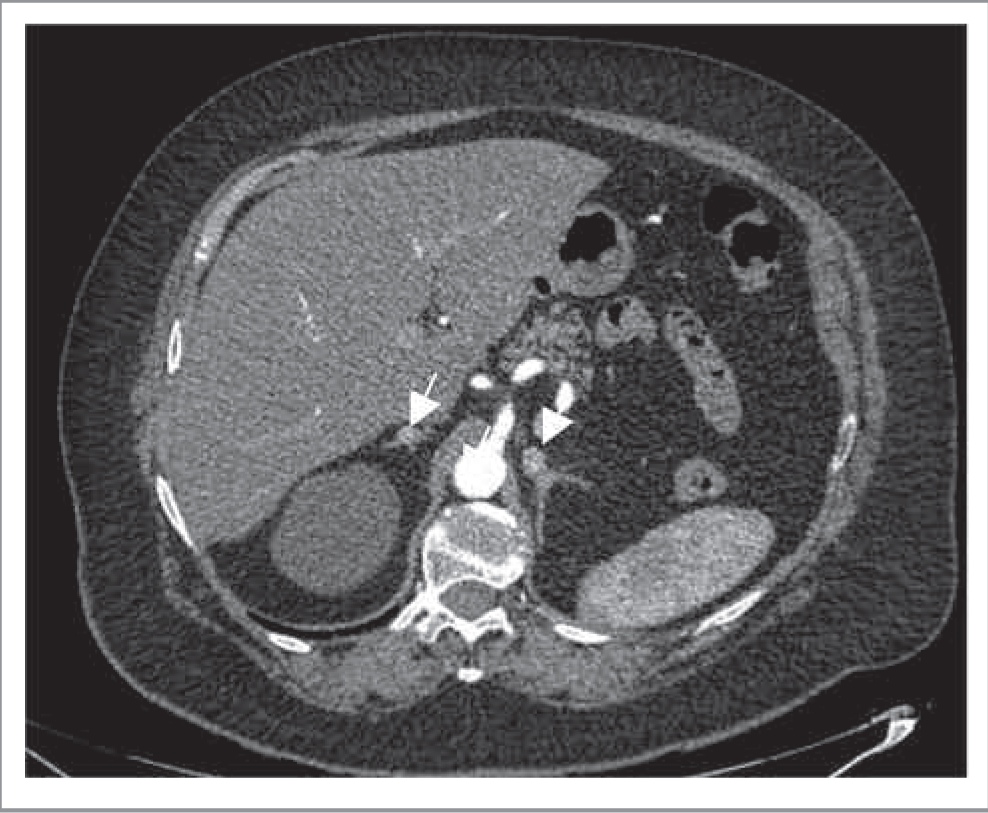

КТ-критерии метастатического поражения часто сходны с таковыми при АКР. Для метастазов характеры: нечетко очерченные контуры, высокая плотность образования (более 15 ед. Н), неоднородность структуры, а также слабое вымывание контрастного препарата при болюсном контрастном усилении. Однако небольшие по размеру метастазы могут быть однородными, в то время как атипичные аденомы, наоборот, могут быть неоднородными. Гиперконтрастные метастазы (например, рака почки) следует дифференцировать с феохромоцитомой (рис. 9). Двустороннее поражение надпочечников более характерно для метастазов, чем для аденом (50% против 10–20%) [11]. Кроме того, в отличие от аденом, метастазы значительно быстрее растут при динамическом КТ-контроле через 6 мес.

Рис. 9. Метастазы светлоклеточного рака почки в надпочечники. МСКТ, аксиальная проекция, АФ. Гиперденсные округлые солидные образования в телах обоих надпочечников.